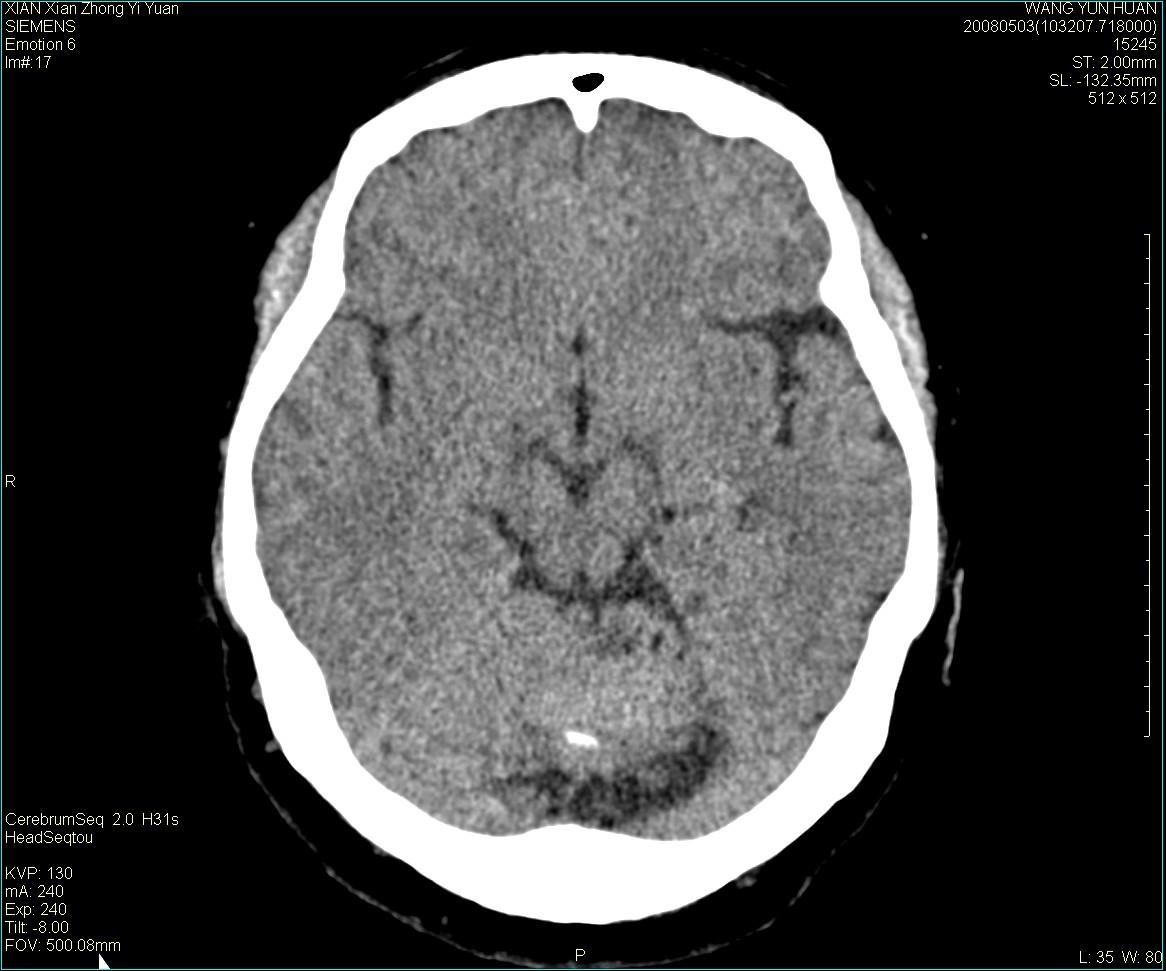

标题: CT13219:(补充强化)请会诊,患者女,60岁,头晕,大家看 [打印本页]

标题: CT13219:(补充强化)请会诊,患者女,60岁,头晕,大家看

病灶显示轻度强化,ct增加4hu左右,大家看是什么肿瘤.

强化后动脉期及延迟2分钟,五分钟图像

小脑蚓部占位,考虑脑膜瘤。增强吧

小脑蚓部囊型肿块,内有实性结节及钙化点。增强后囊壁及结节轻度强化。

考虑蚓部星形细胞瘤(ⅱ级可能性大)。

小脑蚓部肿块,周围无明显占位效应及水肿带,增强轻度强化,考虑低分级星形细胞瘤。